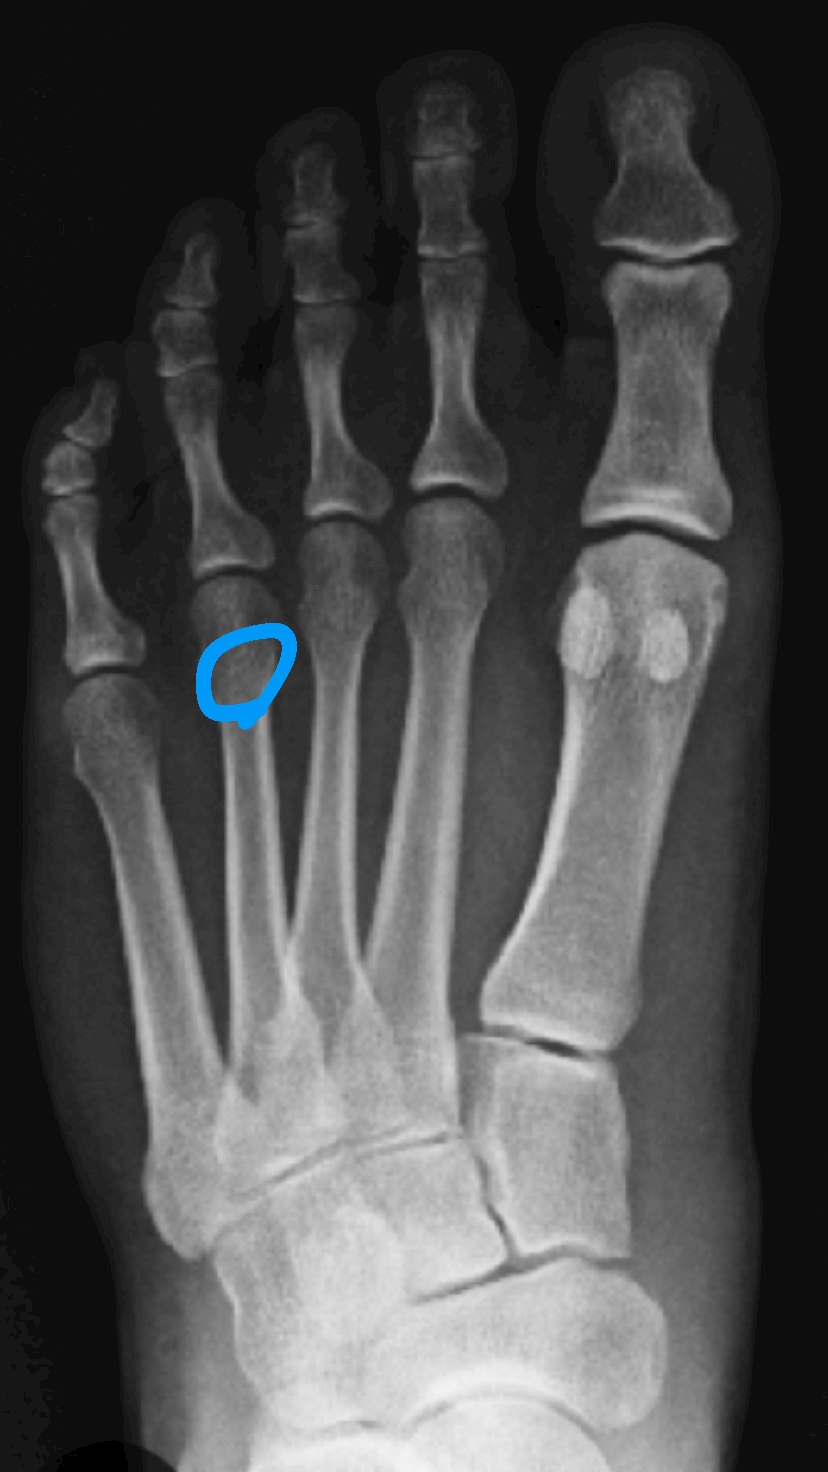

⬆️この部分にヒビ入った

⚠️せにゃんの足のレントゲンじゃないよ🎶拾い画♡